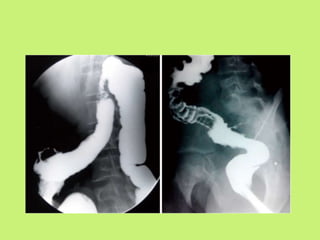

In esophageal TB, barium swallow may show ulceration,

stricture or traction diverticulum.

Long segment circumferential

narrowing in first and second

part of duodenum.

Barium enema study

• The thickening of ileocaecal valve with triangular

appearance, pulled up caecum and/or wide gaping of

the valve with narrowing of the terminal ileum (an

inverted umbrella sign, or Fleischner’s sign.

• Rapid transit and lack of retention of the barium in an

inflamed segment of the small bowel constitutes

Stierlin’s sign”)

• A persistent narrowing or stenosis of the bowel leads

to consistent narrowing of stream of barium called the

“string sign”.